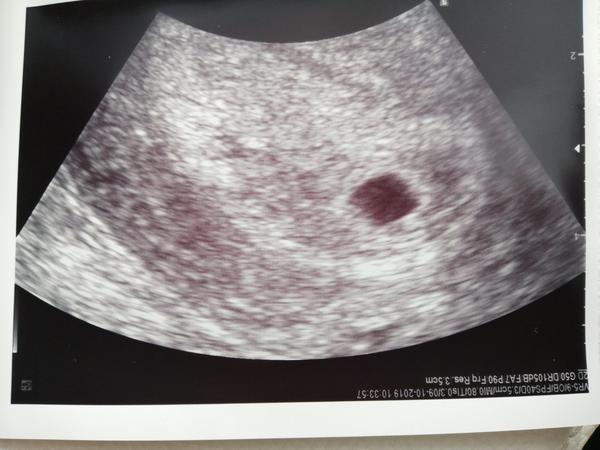

Můj poslední test a prvni ultrazvuk

Pěkně naprd. 😀 Kouzelnou formulí - jsem v prvním trimestru se moderní medicína stává bezzubou, takže ležím na neschopence a smím pít jen čaj. Začalo to migrénou, pokračuje nachlazením. Jinak by utz jsem byla včera - zatím je tam jen černá tečka, takže za dva týdny kontrola. Je to moje první těhotenství, takže všechno je nové...trochu mě bolelo břicho, asi jak se fazolka zavrtávala, ale když jsem chodila, bylo to lepší 🙂 takže tak...